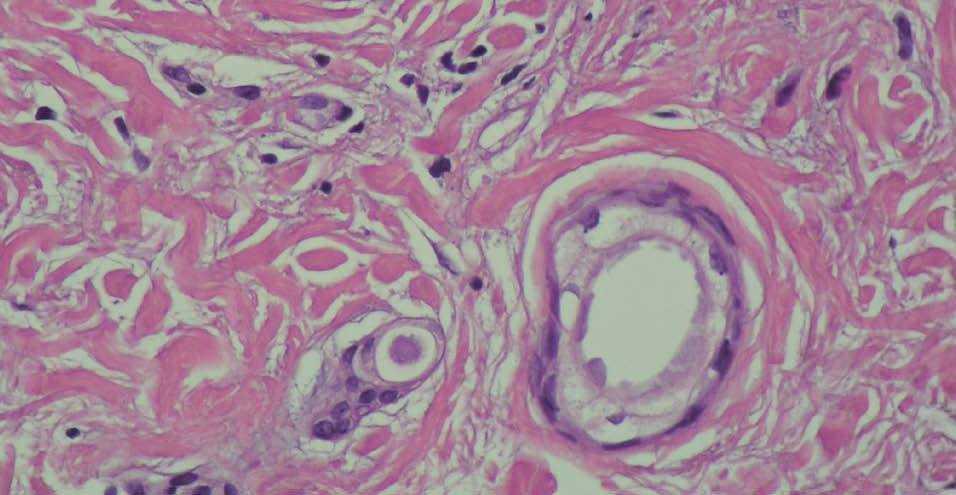

Fig. 2.--Imagen histológica de una de las lesiones.

En la dermis se observaron ductos de pequeño tamaño agrupados, algunos de ellos con una morfología «en coma».

Desde el punto de vista histológico los siringomas son tumores dérmicos formados por ductos pequeños que se agrupan. Estos ductos están constituidos por dos líneas de células cuboidales. En algunas ocasiones los ductos adquieren una forma en coma o contienen un material eosinófilo. Alrededor de estos ductos existe con frecuencia un estroma fibroso. Intercalados pueden verse grupos de células con aspecto basaloide 6,7.